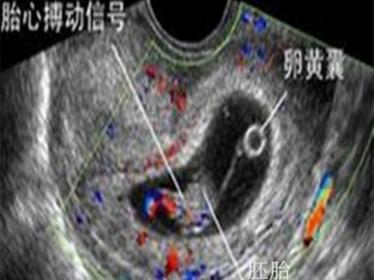

孕6~8周,观察胎芽、胎心发育情况:B超检查

在这个阶段应该能看到宝宝的胎芽了,并能检测到胎心的搏动。